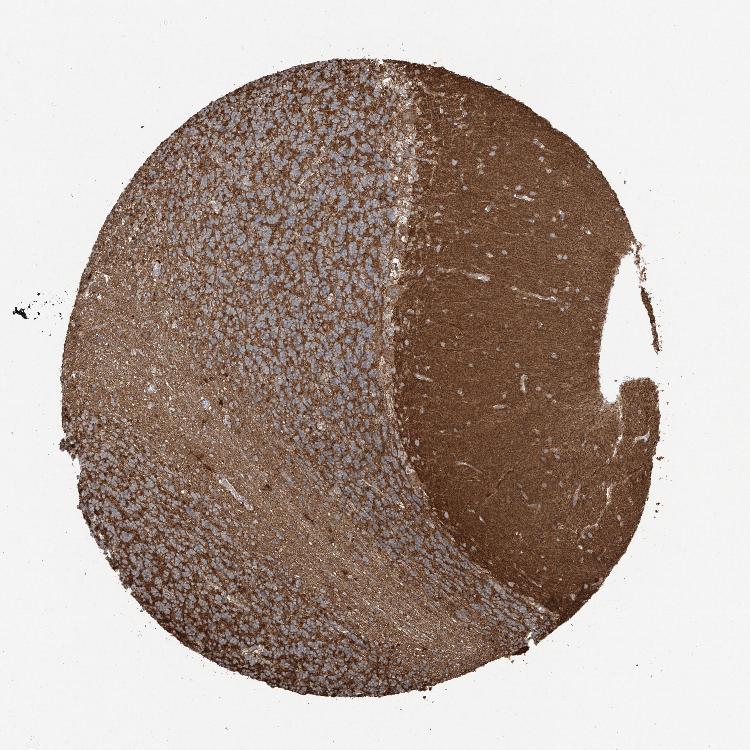

CEREBELLUM - Antibody stainingi

Antibody staining in the annotated cell types in the current human tissue is reported as not detected, low, medium, or high, based on conventional immunohistochemistry profiling in selected tissues. This score is based on the combination of the staining intensity and fraction of stained cells.

Each image is clickable and will lead to virtual microscopy that enables deeper exploration of all samples and also displays staining intensity scores, fraction scores and subcellular localization as well as patient and tissue information for each sample.

Antibody HPA032073Antibody HPA032074

Purkinje cells HighMedium

Cells in granular layer MediumHigh

Cells in molecular layer Not detectedNot detected